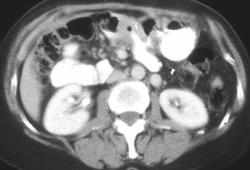

Necrotizing Gastritis